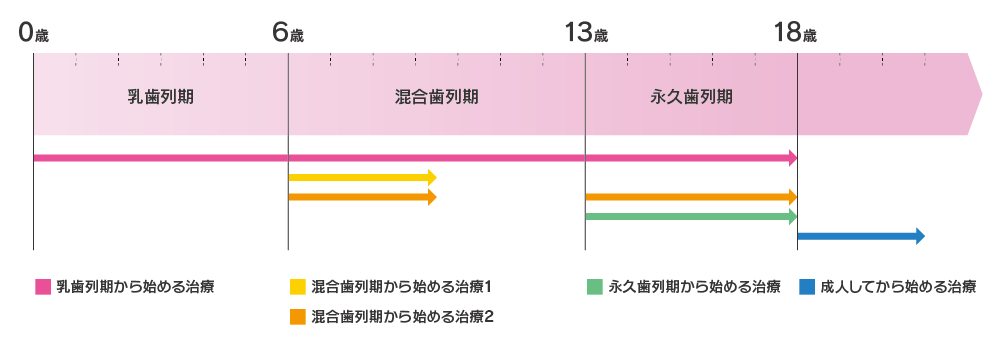

02.矯正治療を始める時期は?

矯正治療を始めるタイミングは、その子の状況によって異なりますが、小学1年生ぐらいが一つの目安だと思います。矯正歯科医の先生の中には、できるだけ早く始める方が良いと言う方もいますが、治療の開始時期は個々の状況によってさまざまです。

例えば、小学1年生ぐらいで治療が必要な子もいれば、もう少し大きくなって小学6年生ぐらいで始めても十分な場合もあります。逆に、小学6年生や中学生ぐらいで治療を希望する子の場合、「もう少し早く来てくれたら良かったのに」と思うこともあります。また、少ないですが5歳、6歳に開始する必要がある場合もあります。

そのため、いつ治療を始めればいいのかは、その子によって大きく違ってきます。相談するタイミングとしては、小学1年生になったら「矯正は必要なの?」「いつ始めればいいの?」といった気になることを矯正歯科医に相談することをお勧めします。

乳歯列期から始める治療

乳歯列期から治療を始めるのは、長期的な通院が必要になり、肉体的にも精神的にも負担が大きいのであまりお勧めできません。ただし、舌を突き出す癖や指しゃぶりがやめられないなど、将来的にかみ合わせに悪影響が出そうな癖がある場合は、それらを改善するためのアドバイスを受けることができます。通院は半年~1年に一度、経過を観察する程度で済むことが多いです。ただし、症状によってはこの時期に治療を開始しなければならない場合もあります。

混合歯列期から始める治療 1

この時期は顎骨の成長期なので、骨格の改善が必要な方は治療を始めます。前歯の反対咬合を改善したり、永久歯が生えるスペースを確保する治療が多いです。この時期に行う治療を「1期治療」と言います。軽度の不正咬合の人は1期治療だけで治療が終了することもあります。1期治療だけで終わる人もいれば、その後、永久歯がすべて生え揃うまで経過観察を続け、永久歯列期に本格的な矯正治療(2期治療)を開始する人もいます。

混合歯列期から始める治療 2

1期治療が終わった後、すべて永久歯に変わるまで経過観察を続け、永久歯が生え揃ったら本格的な矯正治療(2期治療)を始める人もいます。1期治療をすることで、2期治療が短期間で終わったり、より効果的に行えたりすることがあります。

永久歯列期から始める治療

この時期を過ぎると、顎骨の成長は落ち着いてくるので、骨格の矯正は難しくなります。しかし、その分歯の移動計画が立てやすくなるのも事実です。また、この頃には見た目を気にし始めるので、自分から進んで矯正治療に取り組む人が増えてきます。

成人してから始める治療

この時期は、あごの骨の成長がほぼ終わっている時期です。あごの手術が必要な場合や、手術が必要かどうか判断が難しい症状の場合は、あごの成長が終わるまで観察し、その後に矯正治療を始める方が良いこともあります。あごの成長は、女性は16歳ごろ、男性は18歳ごろにほぼ終了します。